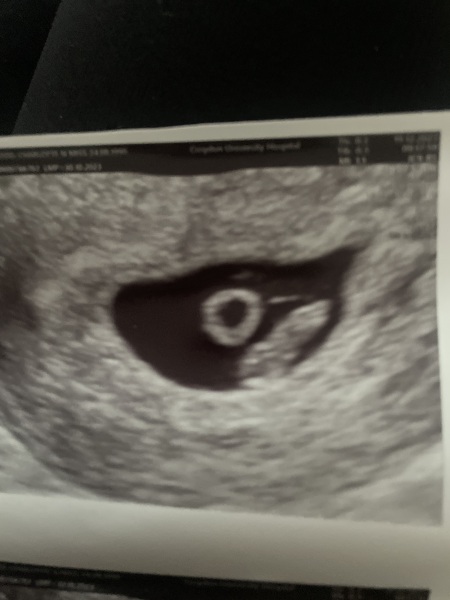

CharTT33 · 19/12/2023 11:14

Hey guys,

I've had my 7 week 1 day scan and we have a healthy heartbeat! Everything measuring perfectly! I’ve had 3 MCs consecutive never got this far yet ! I am sooo happy!! I burst into tears in room while scanning… 🥰

Sending everyone hugs! Xx

@CharTT33 Big congratulations on your lovely scan photo, what a feeling 😊